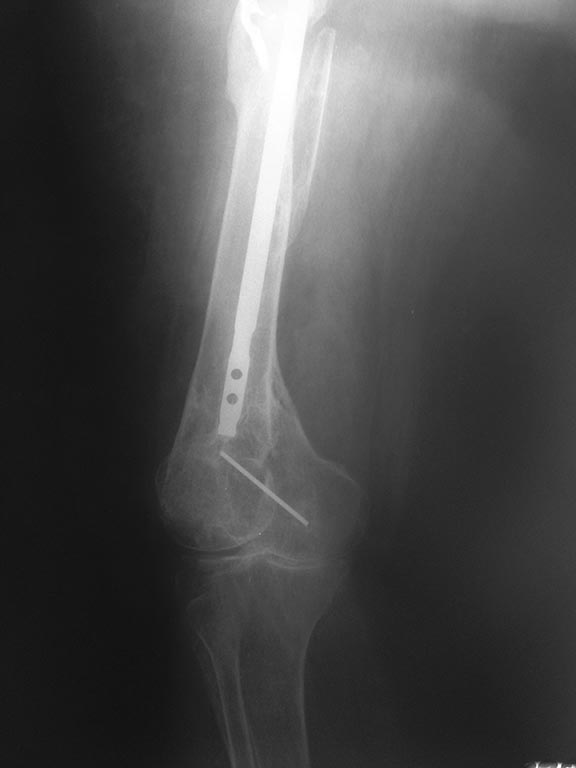

здравствуйте уважаемые коллеги. нужна помощь в дальнейшей тактике по пациентке 62 года вес около 90 кг . передвигается при помощи костылей .

В 2011 году остеосинтез правого бедра на данный момент ложный сустав шейки правого бедра. что бы отправить на ВМП нужно удалить металл, боимся за диафиз бедра. как поступить и кто сможет помочь?

И для планирования, конечно, этого одного снимка мало - надо все бедро видеть, и зону бывшего перелома особенно хорошо. То ли там схватилось, то ли надо сразу планировать длинную ревизионную ножку, чтобы перекрыть эту зону.

еще снимки

Оптимальный вариант - все сделать в одну операцию. Но если это невозможно организационно, можно удалить стержень. Пациентка ходит на костылях - полной нагрузки не будет из-за ложного сустава шейки. Если после эндопротезирования возникнет подвижность на уровне диафиза - остеосинтез пластиной и костная пластика. Если подвижность возникнет сразу после удаления стержня - все сделать в обратной последовательности (пластина, костная пластика, протез). Безусловно, наличие ревизионной ножки расширило бы возмозможности решения проблемы.

Что с коленным суставом? Судя по снимкам, можно предположить наличие гонартроза. Если это так, то абсолютно беспроигрышным вариантом представляется тотальное интрамедулярное замещение бедренной кости, гвоздь удаляется в эту же сессию. Имеем три в одном: искусственный тазобедренный сустав, искусственный коленный, риск перипротезного перелома исключён. Конечно вопрос бюджета